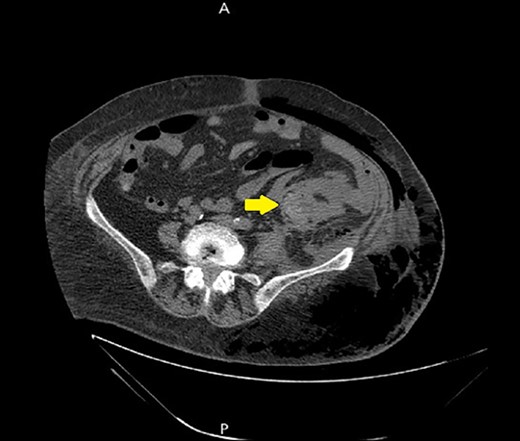

Ultrasound showed extensive subcutaneous soft tissue edema with hyperechoic areas seen in the proximal anterolateral part of the thigh. The initial diagnosis of the condition was a left iliopsoas abscess. Due to the severity of the patient’s symptoms, a non-contrast abdomen and pelvis computerized tomography (CT) scan was done (Fig. 3), which showed a large amount of subcutaneous emphysema within the left flank soft tissues that wrapped anteriorly along the left lower lateral abdominal wall with a small tract of air extending from the left retroperitoneum posterior to the left kidney and extending along the left iliopsoas muscle inferiorly. A skin defect with the underlying abscess collection and air–fluid level was noted (Fig. 4). Another CT scan section saw a soft tissue mass lesion at the distal descending colon (Fig. 5). The abscess drainage was done under CT guidance.

A non-contrast abdomen and pelvis CT scan, which shows a large amount of subcutaneous emphysema within the left flank soft tissues (lower arrow) that wrapped anteriorly along the left lower lateral abdominal wall into the anterior subcutaneous soft tissues of the left lower quadrant (upper arrow). There was also a small tract of air extending from the left retro peritoneum posterior to the left kidney and extending along the left iliopsoas muscle inferiorly (middle arrow).